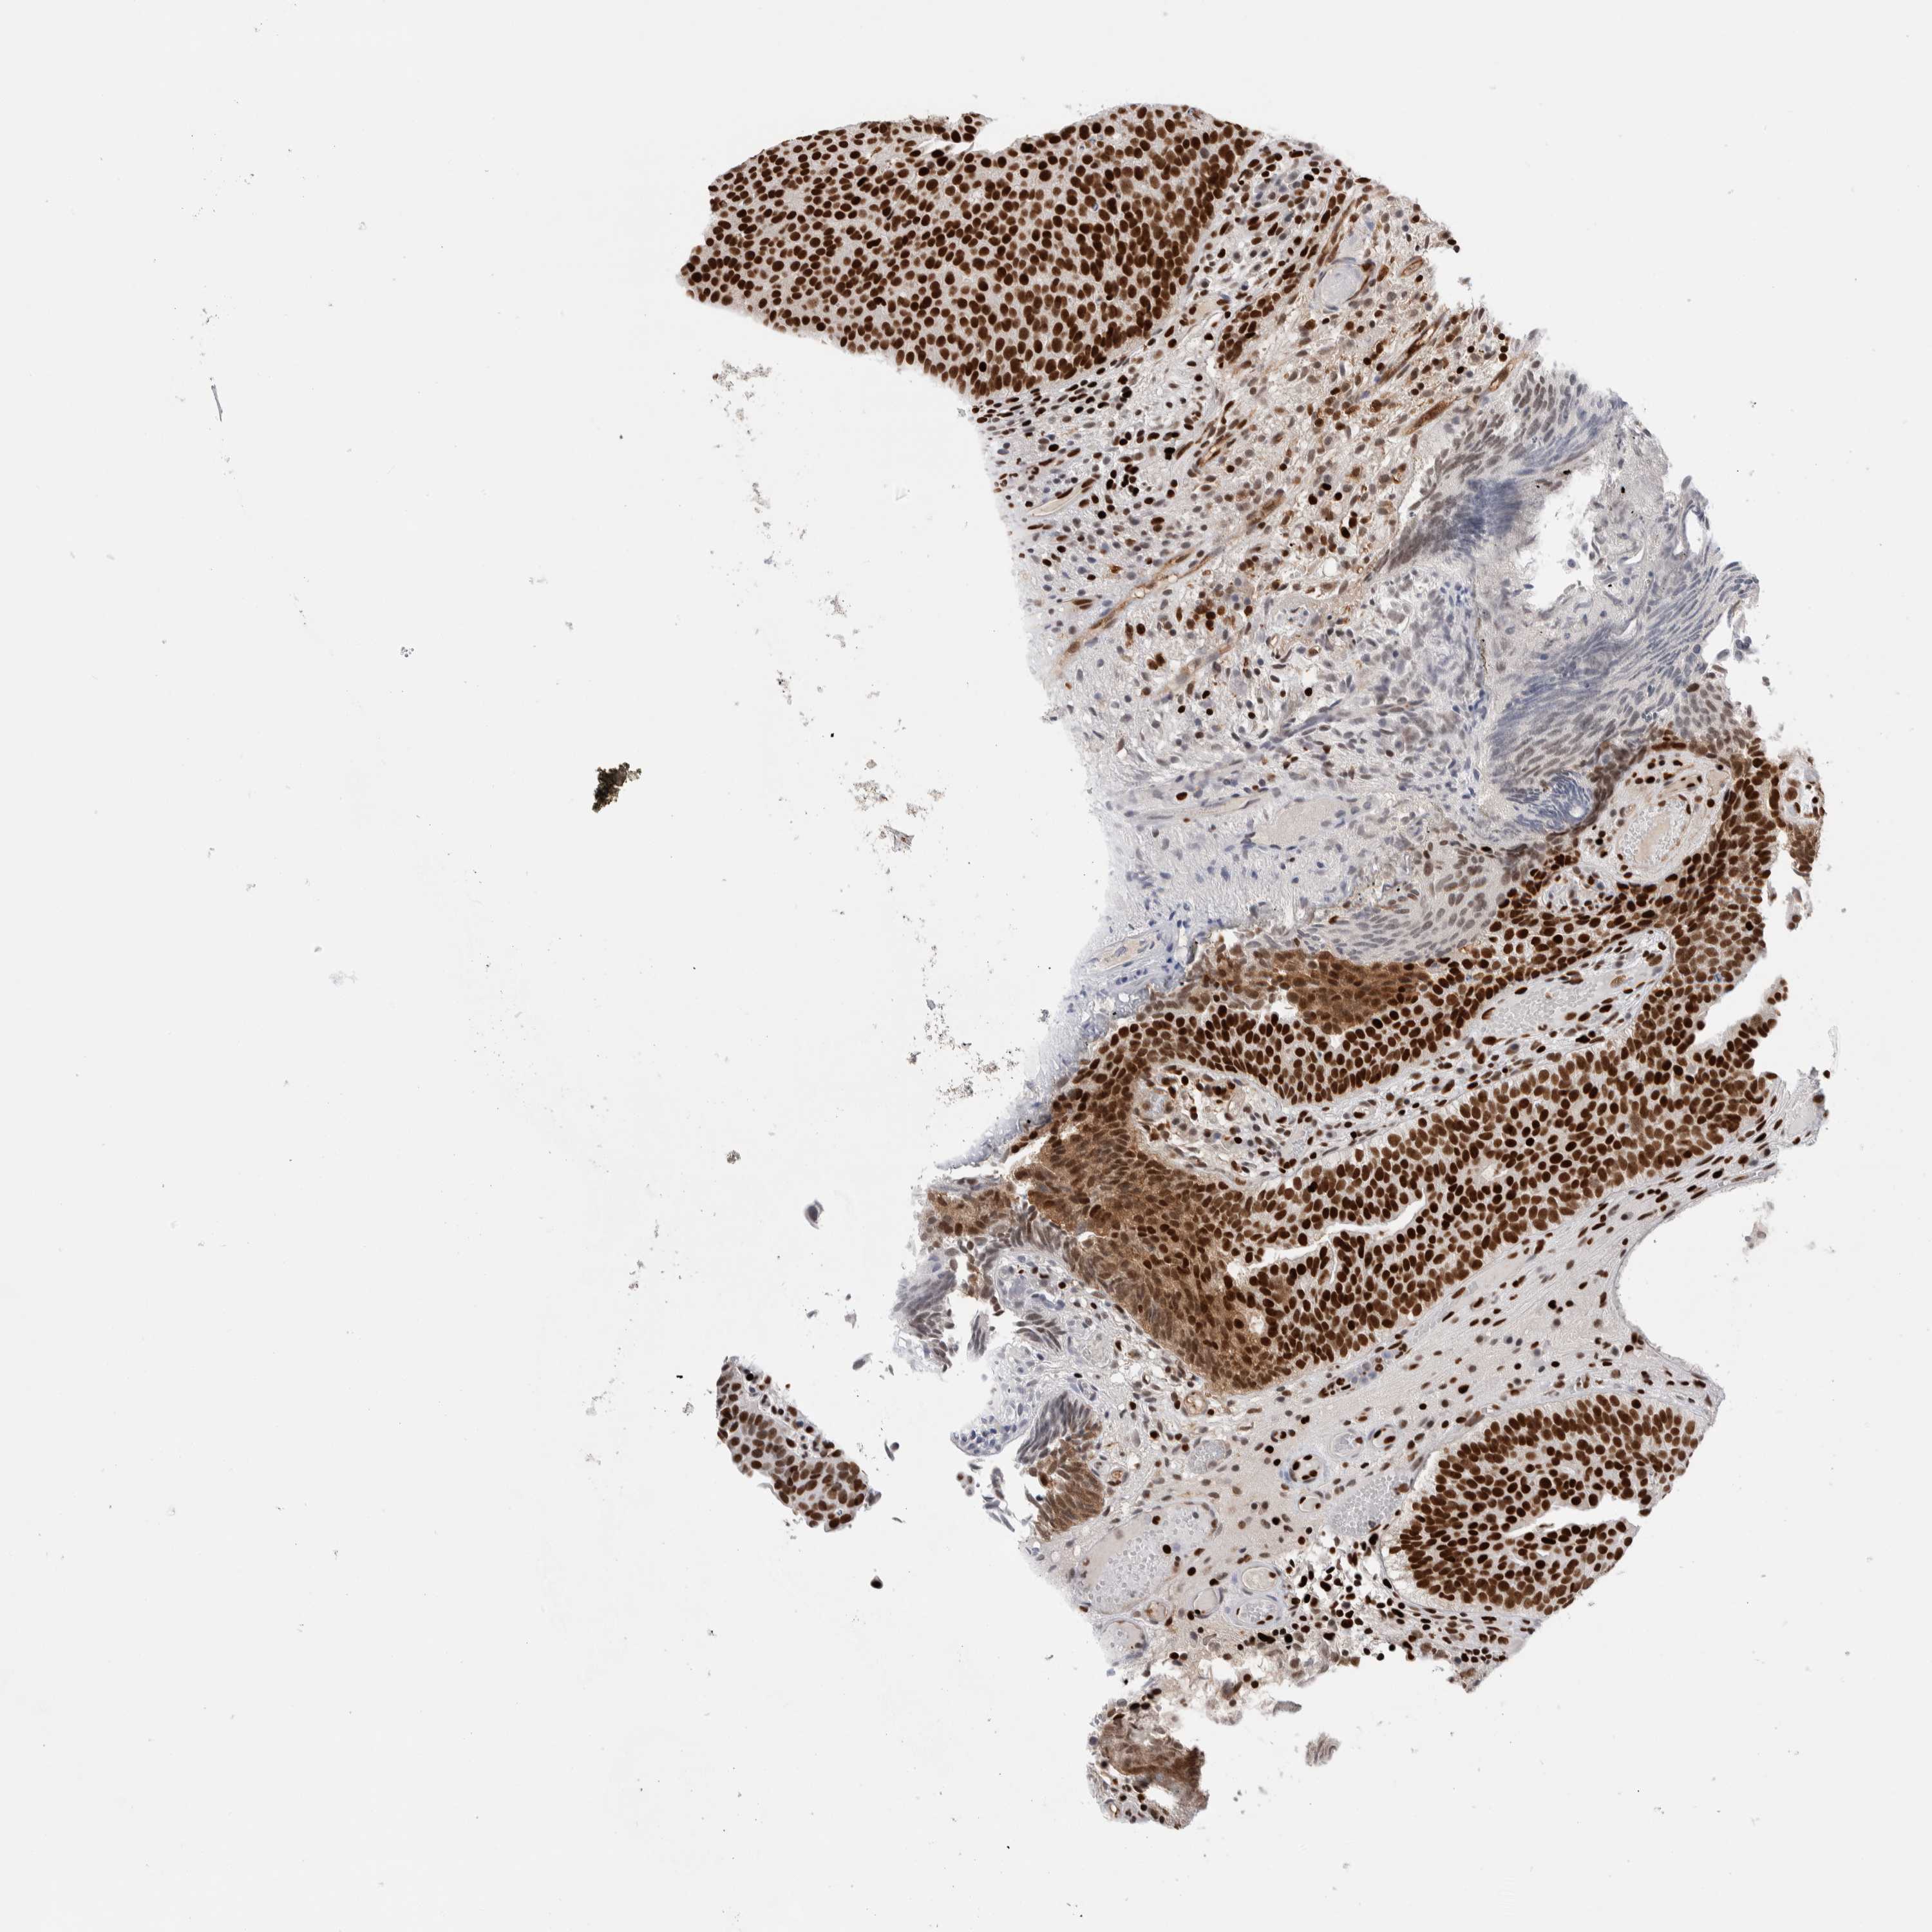

UROTHELIAL CANCER - Protein expressioni

A mouse-over function shows sample information and annotation data. Click on an image to view it in a full screen mode. Samples can be filtered based on level of antibody staining by selecting one or several of the following categories: high, medium, low and not detected. The assay and annotation is described here.

Note that samples used for immunohistochemistry by the Human Protein Atlas do not correspond to samples in the TCGA dataset.

Antibody stainingi

Antibody staining in the annotated cell types in the current human tissue is reported as not detected, low, medium, or high, based on conventional immunohistochemistry profiling in selected tissues. This score is based on the combination of the staining intensity and fraction of stained cells.

Each image is clickable and will lead to virtual microscopy that enables deeper exploration of all samples and also displays staining intensity scores, fraction scores and subcellular localization as well as patient and tissue information for each sample.

Antibody HPA022961

Antibody HPA024457

Staining

High

Medium

Low

Not detected

Intensity

Strong

Moderate

Weak

Negative

Quantity

>75%

75%-25%

<25%

None

Location

Nuclear

Cytoplasmic/membranous

Cytoplasmic/membranous,nuclear

Urothelial carcinoma, Low grade

Urothelial carcinoma, High grade